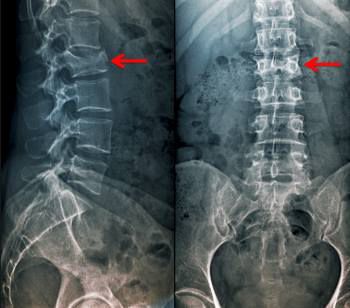

What Is Vertebral Fracture? A spinal fracture is a dislocation or fracture of the vertebrae (backbone) and can occur anywhere along the spine. Most spinal fractures are caused from injury or trauma from car accidents, falls, sports or some sort of high velocity impact.